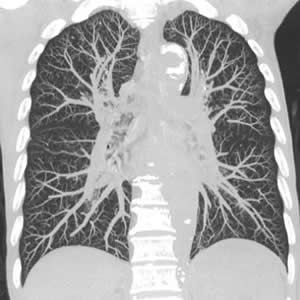

検査は、ベッドに寝ているだけで終了します。また、当院検査は、一回の撮影で同時に複数の輪切り像が得られる最新型ボリュームCTスキャナです。 得られた輪切り画像から下のような精密な立体像を作ることも可能です。

胸部CT撮影が2秒以内で可能

胸部3次元画像